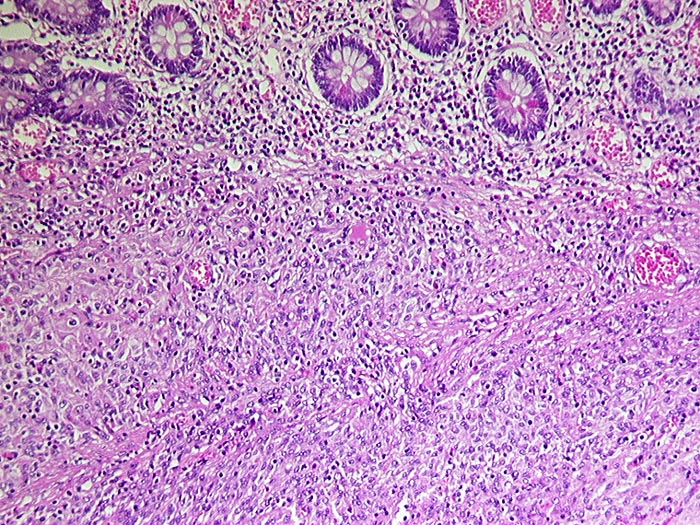

Makroskopisch imponieren kleine Tumoren als peritoneale, intramurale oder submuköse Knoten. Grössere Tumoren wölben sich oft vor und können ulzerieren. Die Schnittfläche ist weisslich und kann Einblutungen, Zysten, Fibroseareale oder Nekrosen aufweisen. Histologisch werden Spindelzelltyp (70%), Epitheloidzelltyp (20%) oder gemischtzelliger Typ (10%) unterschieden. Der histologische Subtyp scheint keinen Zusammenhang mit zugrundeliegender Mutation, Therapieansprechen und Prognose zu haben. Gelegentlich sind vor allem die kleineren Tumoren zellarm und kollagenreich.

• Scharf begrenzter kugeliger Tumor in der Submukosa des Magenantrums

• Über dem Tumor entzündungsfreie Antrumschleimhaut mit partiell reepithelialisiertem oberflächlichem Ulkus (Quellungsfibrinoid).

• Der Tumor besteht aus längs und quer getroffenen Faszikeln spindelförmiger Tumorzellen, welche an glatte Muskelzellen oder Schwannzellen erinnern.

• Herdförmig pseudozystische Auflockerung des Tumorgewebes.